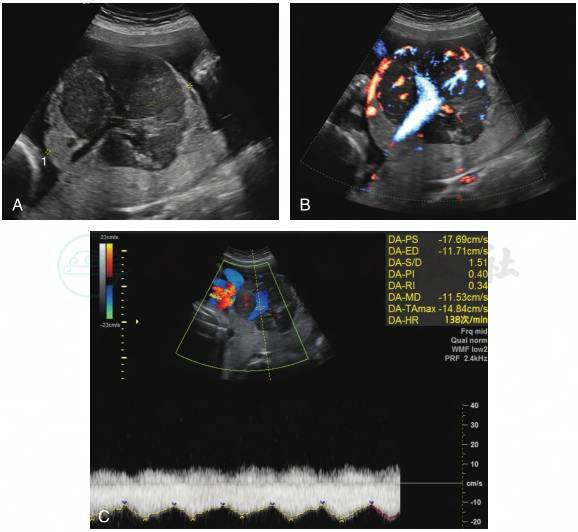

1.超声表现为胎盘内边界清晰、圆形或类圆形实质性包块,回声多低于胎盘组织,常位于脐带根部附近,突向羊膜腔。

2.肿块周边或内部见条索状彩色血流,多普勒频谱为胎儿动脉血流。

3.有时合并羊水过多(图1)。

图1胎盘绒毛膜血管瘤

A.胎盘实质内见边界清晰的中低回声区,突向胎盘胎儿面;B.肿块内部见条索状彩色血流;C.多普勒频谱为胎儿动脉频谱